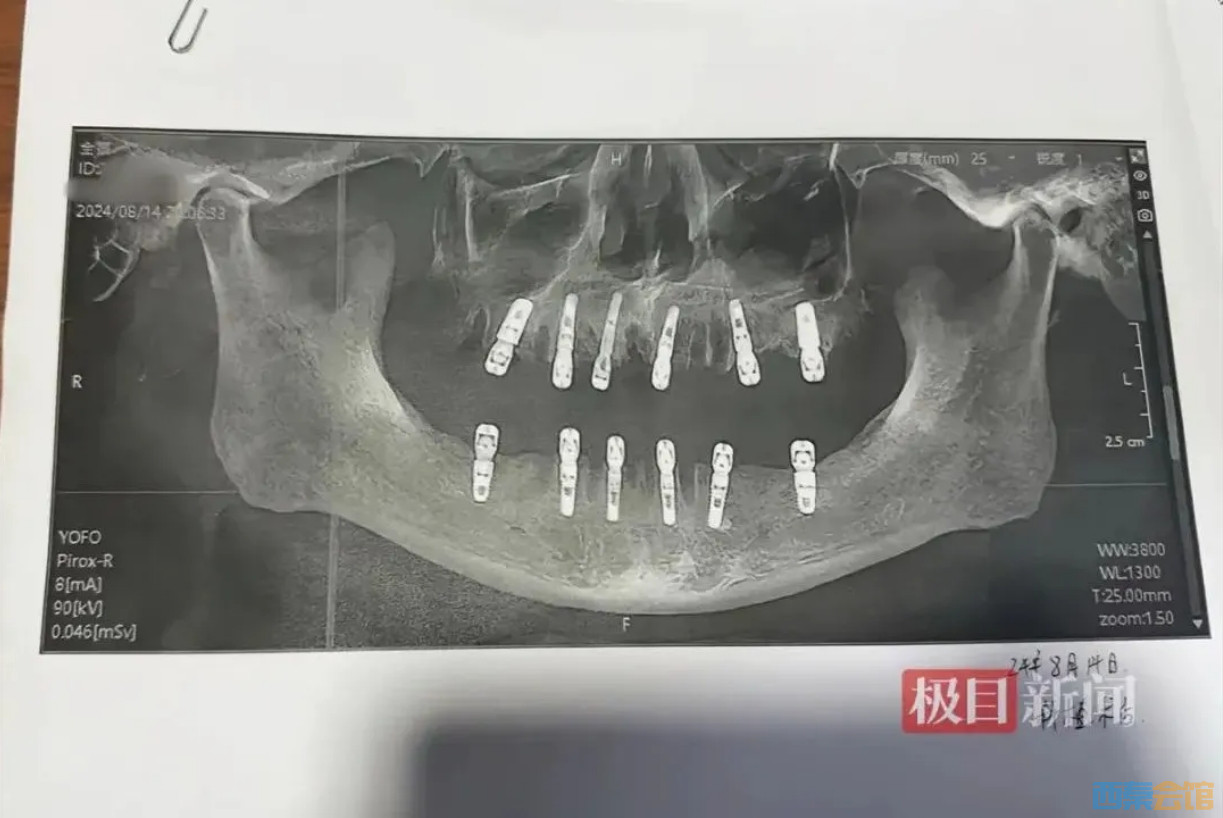

近日,浙江永康市居民舒女士报料称,其父亲黄某在当地德维口腔医院一次性拔除23颗牙齿,并在同日种植12颗牙齿。随后疼痛不止,13天后心脏骤停死亡。

9月3日,记者联系了永康市卫生健康局,其工作人员表示:“由于拔牙和死亡时间相隔13天,黄某具体的死亡原因我们还在调查。” 90.png 89.png 88.png 87.png

随后,德维口腔医院工作人员向记者介绍了种植牙手术须知:“本月种植牙手术费用为每颗1500元,具体一次能拔除多少颗需要由医生进行面诊、确定患者身体情况后再确定。”此外,还介绍说前面的门牙是可以当天拔、当天种的,但是后面的牙齿拔了以后要隔三四个月才能种植。然而,据黄某的种植手术同意书,在其接受的手术中,有多颗臼齿在拔除当天就进行了种植,与工作人员介绍的注意事项不符。